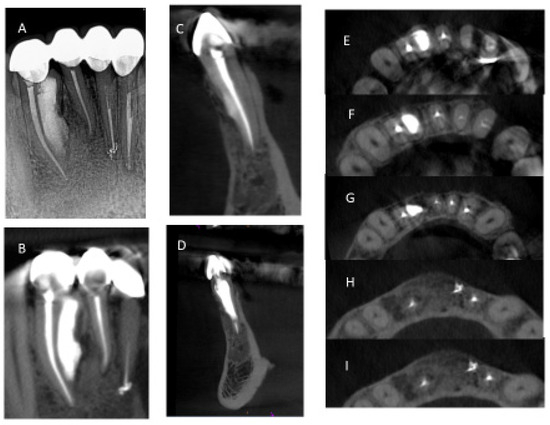

2.2. Nonsurgical Treatment

2.3. Surgical Treatment